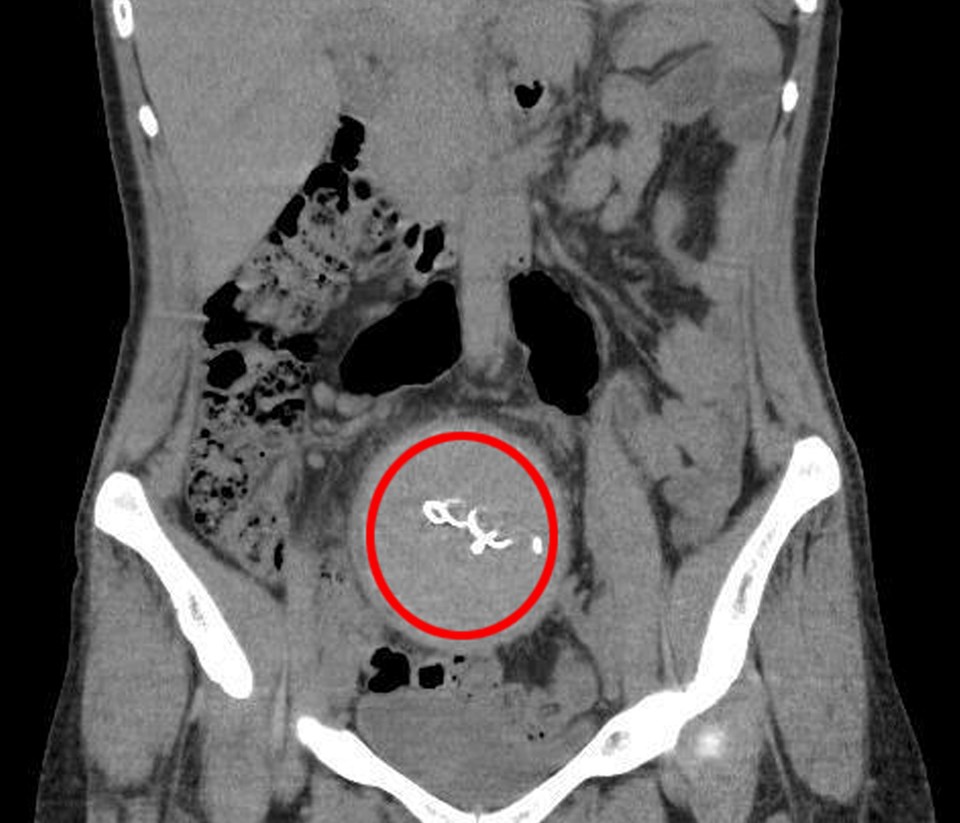

Burada yapılan kontrolde, doktor tomografi istedi. Çekilen tomografide, Y.S.’nin vücudunda doğum sonrası unutulan sargı bezi görüldü.

İhmal nedeniyle 2 yıldır yaşadıklarından dolayı şoke olduğunu belirten Y.S.'nin vücudundaki 30 santimetrelik gazlı bez ameliyatla çıkarıldı.